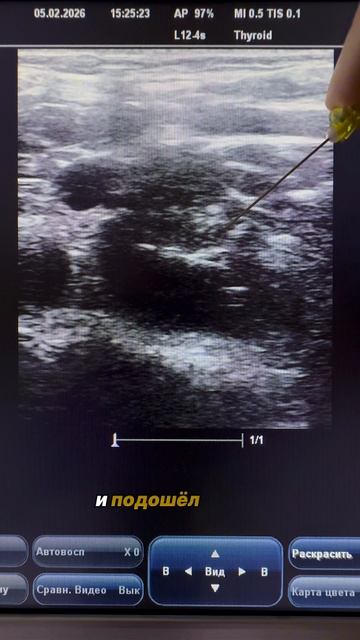

Когда пациент тучный даже при надключичном доступе вена располагается очень глубоко и это сказывается на траектории вводимой иглы Траектория хода иглы получается настолько крутой что с трудом удается контролировать кончик иглы Для профилакт..., видео от 2026-02-05 загрузил на rutube Russian Ultrasound School...